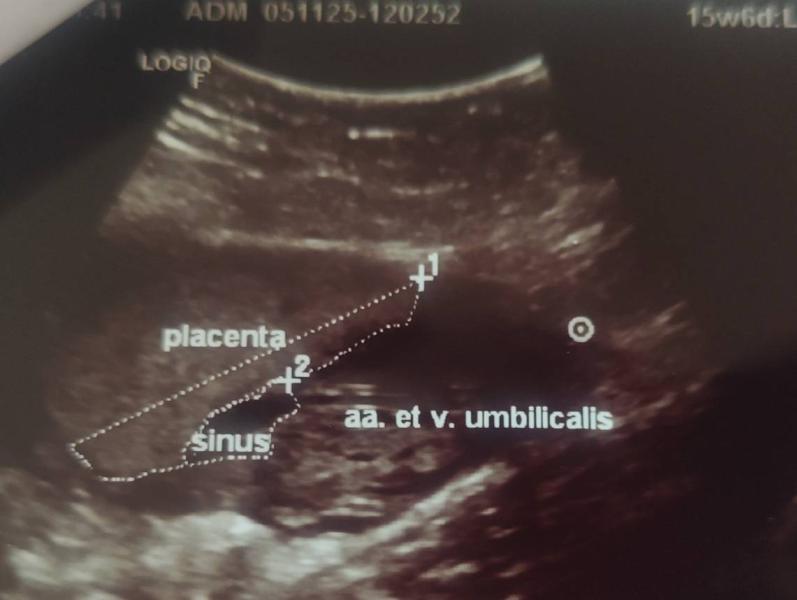

Сегодня не подтвердили оболочечное прикрепление пуповины. Краевое. фуф 😮💨

@momsymom на скрининги не объясняя написали оболочечное. Это мое второе самостоятельно УЗИ после ,на первом засомневались в прикрепление , на этом уже акцент был именно на прикрепление и оно от плаценты